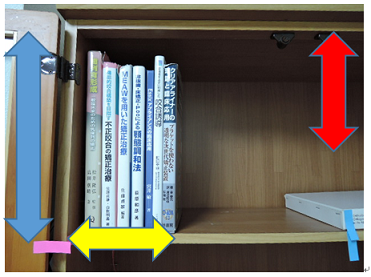

MEAW(マルチループ)を利用して歯を動かす隙間の作り方は2種類あります。

②ふたつ目は以下の様な原理です。

①では歯が近心側に綺麗に傾いた場合ですが、歯が内側(舌側)に傾く事もあります。

この場合もMEAW(マルチループ)によって内側(舌側)に傾むいた歯を起こしていきます。

MEAW(マルチループ)を利用して歯を動かす隙間の作り方は2種類あります。

①ひとつ目は以下の様な原理です。

これを身近な7冊の本を使って説明していきましょう。